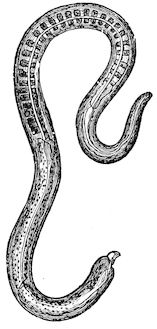

Fig. 2.—Horse suffering from osseous cachexia.

Fig. 3.—Pig suffering from osseous cachexia (fourth stage).

In horses, particularly in riding horses, fractures are commonest in the region of the forearm, cannon bone, and anterior phalanges. So extremely fragile are the bones at this stage that the horse represented herewith broke twelve ribs at one time by simply falling on its side. It is interesting to note that such fractures are never accompanied by any extensive bleeding. They have little tendency to repair, no real callus formation occurs, and on post-mortem examination one often finds the ends unconnected by temporary callus, worn, and rounded by reciprocal friction.

In horses, the different phases of the disease develop precisely as in bovines. The apparent differences between affected horses and cattle result in reality from differences in their capacity for continuing work. In the first phase, horses are incapable of work, their movements being 13badly co-ordinated. They are inclined to stumble, and appear as though suffering from strain of the lumbar muscles.

In the second phase pain referable to the bones sets in. Lameness develops without visible lesions and is rapidly followed by synovitis and arthritis in the lower portions of the limbs, and by wasting and anæmia.

The animals seem unable to move rapidly, or if forced to do so may sustain fractures even at a trot: the limb bones sometimes break or ligamentous insertions in the neighbourhood of joints are torn away, resulting in sudden falls on the ground and fracture of ribs or even of the vertebral column. This corresponds to the third phase, osteoclastia, in oxen.

Fig. 6.—Osseous cachexia. This condition developed in two months, the last month of gestation and the first of lactation.

From then onwards, horses become useless and, if not destroyed, may, after a few weeks or months, develop the condition known as osteomalacia, in which the flat bones become softened, the head, the branches of the lower jaw and the face become deformed, while mastication and other functions are impeded.

Germain gives the above symptoms as characteristic of the mode of development of the disease in French and Algerian horses imported into Tonquin, and his description, written several years ago, is fully confirmed by more recent observations. Since Tonquin was taken over by the French, however, improved methods of culture have resulted in the production of better cereals and forage; the fodder plants have been vastly improved, to the great benefit of imported animals.